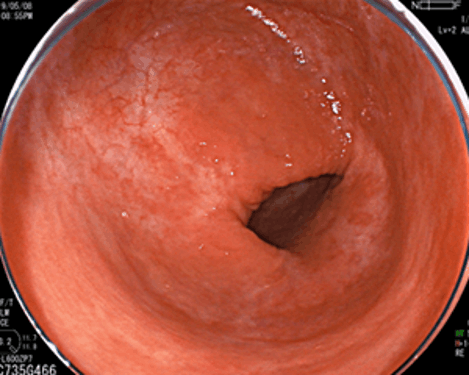

こちらは激しい炎症が治癒した後の瘢痕像です。潰瘍性大腸炎は早期に発見して治療を開始することによって、日常生活が送りやすくなるだけでなく、急な増悪から入院になってしまったりする可能性を下げることもできます。また治療で炎症をコントロールし、定期的に大腸カメラを行うことで、炎症由来の大腸がんの発生を抑制し、さらに大腸がんを早期発見することが可能となります。健診での便潜血検査陽性や、下痢・排便時に血が混じるなどの症状が続く際には、放置することなくきちんと消化器病専門医・内視鏡専門医を受診するようにしましょう。